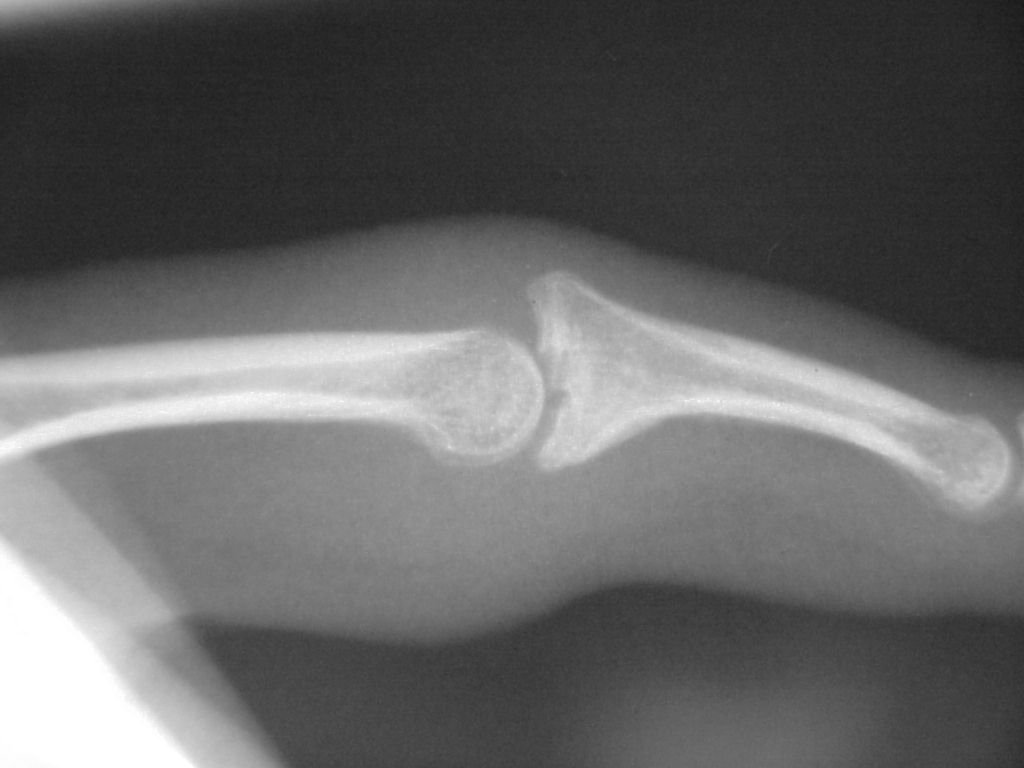

Xrays show an apparently healed PIP fracture dislocation with dorsal subluxation - but concentric tracking of the abnormal palmar articulation.

First impression was that the palmar fragment was probably big enough to take down and reinsert. However, comparison of films shortly after the fracture (above) and at two months (below) confirms the injury as a healed comminuted central impaction fracture with splay and hinging of the volar cortex.